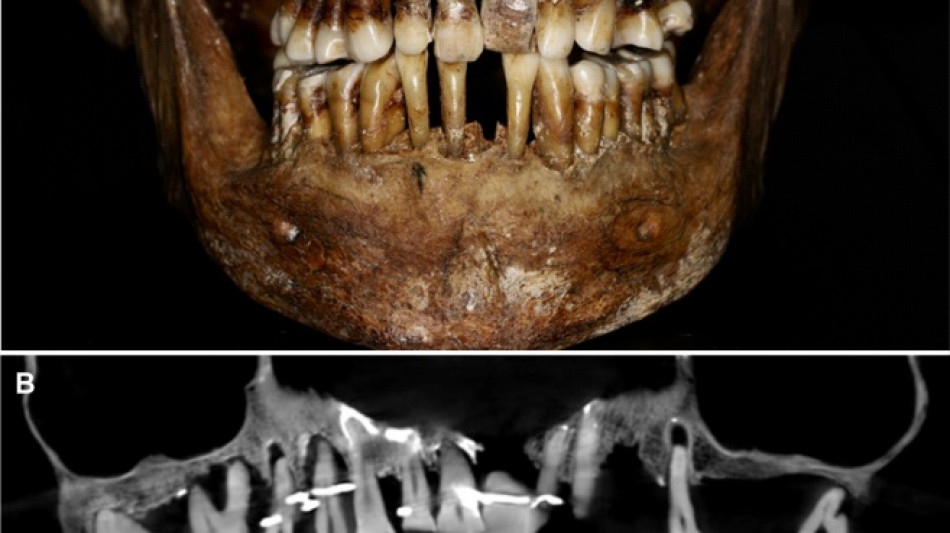

French aristocrat's golden dental secret revealed 400 years on / Photo: Handout - INRAP/Rozenn Colleter/AFP/File

Embalmed in a lead coffin, her skeleton -- and teeth -- were remarkably well preserved.

A "Cone Beam" scan, which uses X-rays to build three-dimensional images, showed that gold wire had been used to hold together and tighten several of her teeth.

She also had an artificial tooth made of ivory from an elephant -- not hippopotamus, which was popular at the time.

The gold wires would have needed repeated tightening over the years, further destabilising the neighbouring teeth, the researchers said.